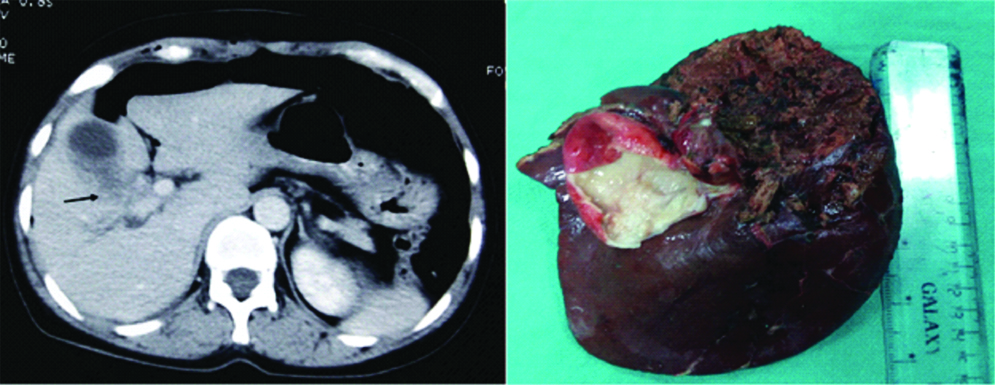

Computed Tomography (CT) scan (left) and intraoperative image (right) of patients with gallbladder cancer with right portal pedicle involvement (arrow) requiring extended right hepatectomy.